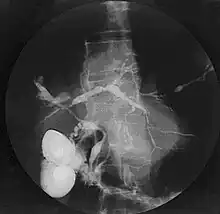

| Cholangiogram of primary sclerosing cholangitis | |

Historically, a cholangiogram would be obtained via endoscopic retrograde cholangiopancreatography (ERCP), which typically reveals "beading" (alternating strictures and dilation) of the bile ducts inside and/or outside the liver. Currently, the preferred option for diagnostic cholangiography, given its noninvasive yet highly accurate nature, is magnetic resonance cholangiopancreatography (MRCP), a magnetic resonance imaging technique. MRCP has unique strengths, including high spatial resolution, and can even be used to visualize the biliary tract of small animal models of PSC.[21]